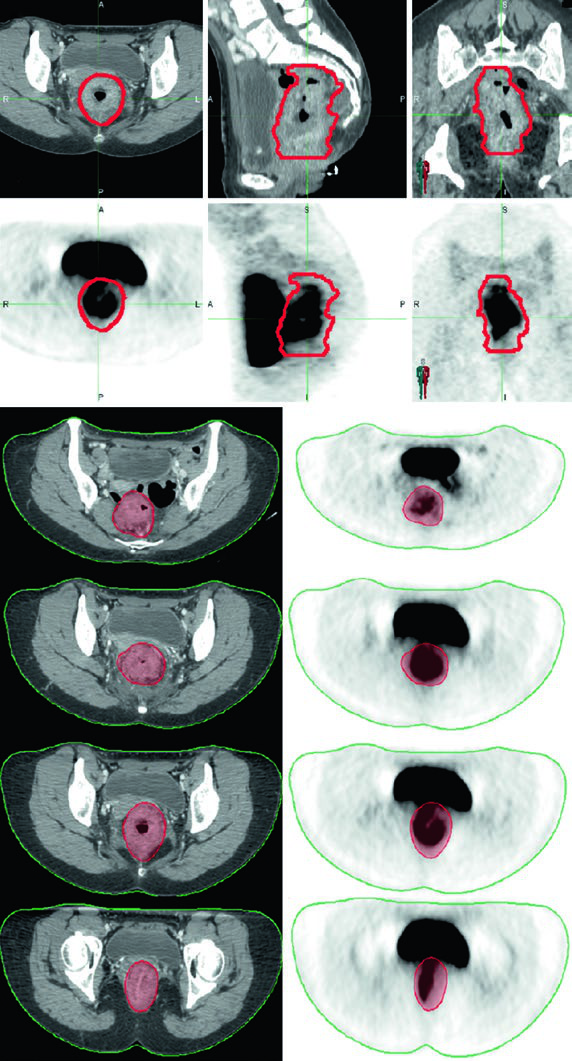

PET/CT can help delineate gross disease, but areas of low radiotracer uptake should not supersede physical, endoscopic, or CT/MRI findings. In practice, PET/CT fusion with the planning CT is most useful for confirming GTV extent rather than replacing other imaging modalities.

CT simulation with intravenous contrast and slice thickness of 3 mm or less is mandatory. Oral contrast may help delineate small bowel loops. Fusion with diagnostic PET/CT or MRI improves target delineation accuracy. Bladder filling protocol deserves careful consideration — a full bladder limits the volume of bowel within the pelvis, while an empty bladder provides better day-to-day reproducibility.

The primary GTV (GTV-P) encompasses all gross disease identified on physical examination, endoscopy, and imaging. The nodal GTV (GTV-N) includes all visible perirectal, mesorectal, and involved iliac lymph nodes. In the absence of biopsy, any lymph node in doubt should be included as GTV. Low-lying rectal tumors require attention to the inguinal nodes, and tumors with anterior invasion into adjacent organs warrant evaluation of external iliac nodes.

The high-risk CTV (CTV-HR) should include the GTV with a minimum 1.5 to 2 cm superior and inferior margin, plus the entire rectum, mesorectum, and presacral space. For grossly involved external iliac or inguinal nodes, the GTV-to-CTV margin should be at least 10 to 15 mm. In T4 tumors, a 1 to 2 cm margin into adjacent invaded organs (bladder, prostate, cervix) is added.